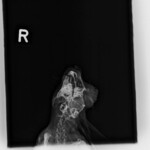

Pirátka Amálka již odcestovala do nového domova. Domov našla v Olomouci a i nadále bude pravidelně navštěvovat MVDr Agátu Sívkovou, která se o ní celou dobu skvěle starala. Amálce se pomoci dostalo opravdu na poslední chvíli. Její majitelé absolutně zanedbali péči o ní a pomoci se jí dostalo opravdu za 5 minut 12. První operaci podstoupila v psím azylu Zastavme utrpení z.s. a nadále jsme Amálku přijali pod svá ochranná křídla my. Díky vážnosti jejího stavu byla Amálka po celou dobu léčby v dočasné péči veterinářky, která dohlížela na její zdravotní stav. Podstoupila CT vyšetření a několik složitých operací (včetně sekání jařmové kosti) a i přesto, že její šance na přežití byly 50 na 50 jsme velice rádi, že jsme to nevzdali. Amálka je již v rámci možností v pořádku. Její zdravotní handicap ani komplikovanější povaha neodradila vážnou zájemkyni a králičce se tak naskytla skvělá příležitost nového domova v Olomouci kde jí budou dělat společnost dva králičí kamarádi Fousek a Albert. My bychom tímto chtěli poděkovat MVDr Sívkové za skvělou péči, MVDr Jeklovi a Hauptmanovi za provedení CT vyšetření a operací a samozřejmě i vám – našim fanouškům, kteří nás podporují a bez kterých bychom nikdy nemohli pomáhat v takové míře v jaké pomáháme a králíčkům bychom tak nemohli poskytnout nadstandardní veterinární péči. Děkujeme, že jste v tom s námi!